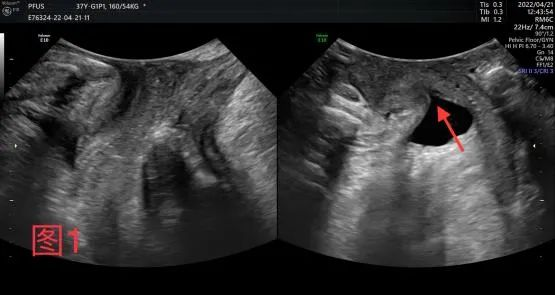

据悉,曾有一名37岁女性患者,因打喷嚏漏尿加重来诊。经盆底超声检查,发现患者不但有压力性尿失禁、膀胱膨出、肛门外括约肌局部损伤的超声表现,还伴有后腔室小肠疝出征象,明确了患者阴道脱垂的主要原因。临床检查不能对阴道脱垂从外部形态做出判断,而盆底超声可以对深部组织情况进行准确评估。盆底超声应用临床以来,充分显示了其优越性。

图1:尿道内口开大呈“漏斗”型(红色箭头)